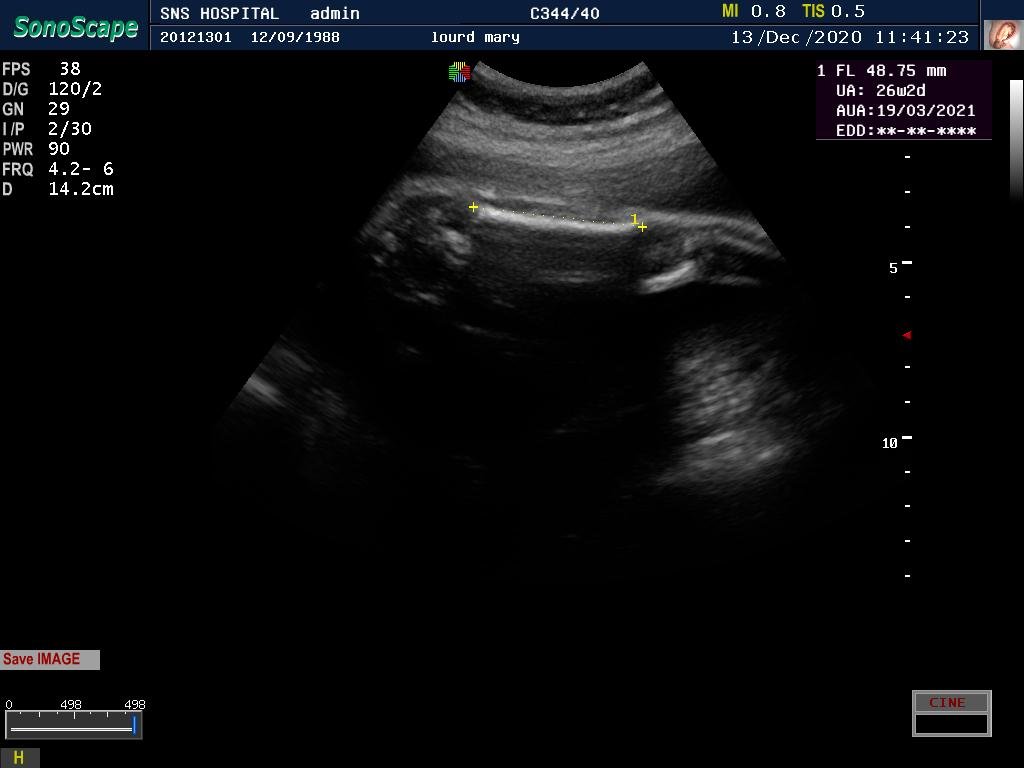

DIAGNOSIS – TYPE 2 DM ON INSULIN WITH INTRA UTERINE GROWTH RESTRICTION

32 yrs, MRS. M, G3P1L1A1 / LMP -03-06-2020 / EDD – 10-03-2021/ previous intrauterine growth restriction with a birth wt of 1.75kg.

Seen first time @ 18 weeks gestation in the month of October.

First visit U/s – 2+, hence was advised GTT., FBS-101 mg/dl, 1hour-206 mg/dl, 2hours-201mg/dl, patient started on INSULIN 5Iu-5Iu

The insulin requirement kept changing as the pregnancy advanced .she was already on aspirin and her uterine Doppler showed low resistance flow. Growth scan with Doppler every 4weeks done from 20 weeks.

There was growth lag of 2weeks @ 27 weeks gestation, Doppler U/A 50th percentile followed by growth scan every 2weeks with Doppler.

The parameters fell below 50th percentile but the interval growth was satisfactory.

Steroids completed @ 33weeks patient had PPROM @ 35 weeks, and delivered an alive preterm vaginal delivery – Boy, 2.2kg.